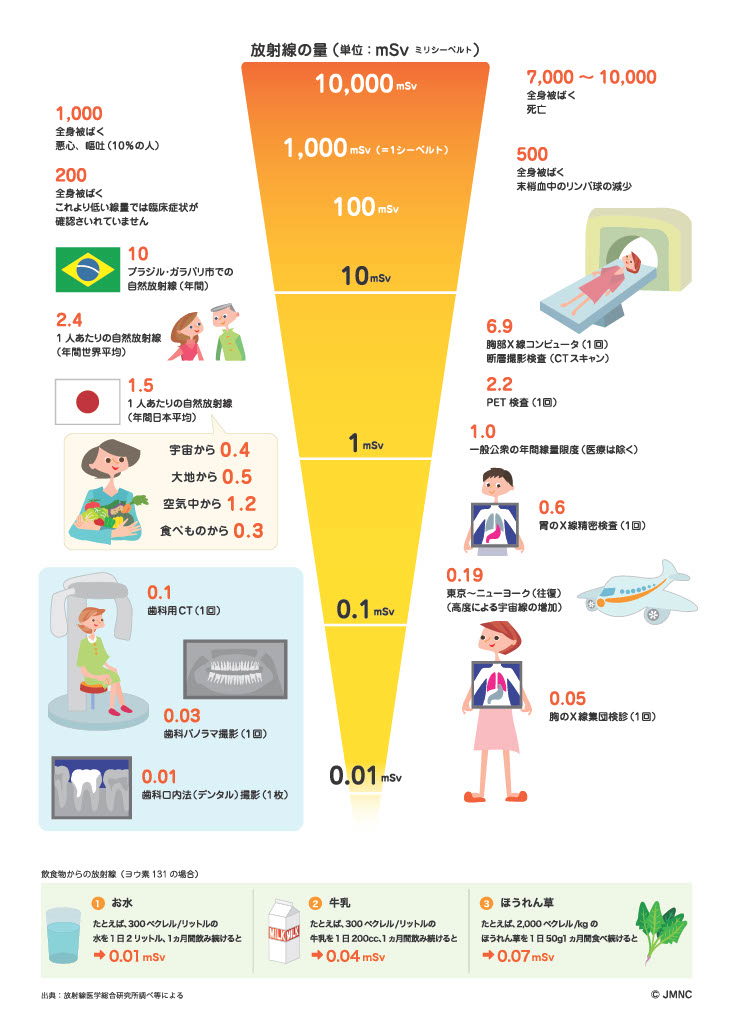

A1.歯科用CTの放射線量は、医科用の胸部CTなどと比較して約10分の1から30分の1程度です。

日本で1年間に自然界から受ける放射線量よりもはるかに少なく、

健康への影響は極めて低いとされています。